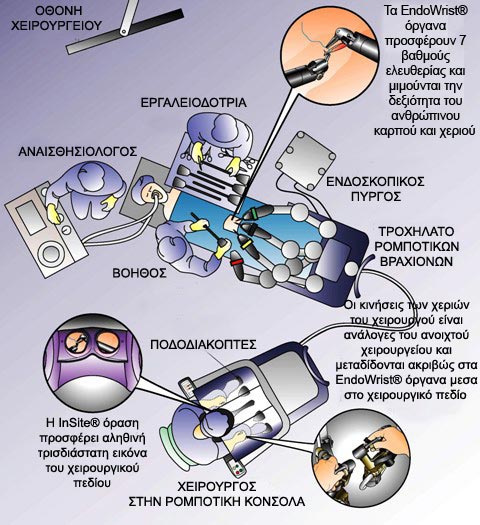

Είναι σημαντικό να υπογραμμισθεί ότι η επέμβαση με το da Vinci δεν εκτελείται από το ρομπότ αλλά ο χειρουργός έχει πάντα τον απόλυτο έλεγχο κάθε χειρουργικού βήματος με την βοήθεια της ρομποτικής χειρουργικής πλατφόρμας.

Επιπλέον ο χειρουργός ελέγχει μία στεροσκοπική οπτική που συνδέεται μία υψηλής ευκρίνειας κάμερα η οποία εξασφαλίζει μία τρισδιάστατη υψηλής ευκρίνειας όραση της εσωτερικής ανατομίας του ασθενή. Ένας έμπειρος χειρουργός λειτουργεί σαν βοηθός και στέκεται δίπλα στο χειρουργικό τραπέζι βοηθώντας τον ρομποτικό χειρουργό κρατώντας ανοιχτό το χειρουργικό πεδίο, αναρροφώντας και καθαρίζοντας, χρησιμοποιώντας όργανα που εισέρχονται μέσα από τα δύο βοηθητικά τροκάρ.

Το ρομποτικό σύστημα da Vinci προσαρμόζεται στα τροκάρ πριν την έναρξη της επέμβασης. Mε τον ρομποτικό χειρουργό να κάθεται μόλις ελάχιστα μέτρα δίπλα από το χειρουργικό τραπέζι στην χειρουργική κονσόλα, τα ρομποτικά όργανα ελέγχονται από τον χειρουργό σε πραγματικό χρόνο με υψηλή ακρίβεια κλιμακωτής κίνησης.

Σχηματική εικόνα της διάταξης της χειρουργικής αίθουσας για την νευροπροστατευτική ρομποτική ριζική προστατεκτομή